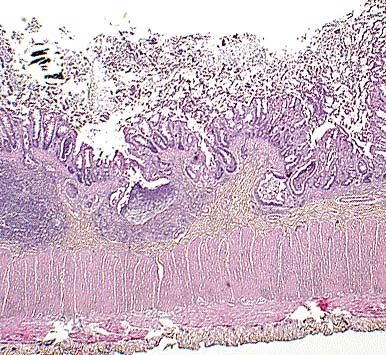

Necrotizing colitis in a tamarin monkey. (HE, 40X, 73K)

Multinucleate viral syncytial cell in crypt in a tamarin infected with measles virus. (HE, 400X, 66K)

Crypt herniation in a measles-infected tamarin. (HE, 100X, 106K)

Contributor's Diagnosis and Comments: Colon: Colitis, acute, diffuse, moderate, with epithelial syncytial cells and intranuclear inclusion bodies. Etiology: Paramyxovirus infection, most likely measles.

The histologic changes in the colon (epithelial necrosis, epithelial syncytial cells and intranuclear inclusion bodies) are consistent with infection with a paramyxovirus. A careful microscopic search of multiple organs, including spleen, liver, lymph nodes and lung failed to demonstrate involvement of any other organ. Callitrichids are susceptible to parainfluenza virus, measles (morbillivirus) virus, and Paramyxovirus saguinus. Parainfluenza is characterized clinically by upper and lower respiratory tract disease. Measles in New World primates can manifest as a respiratory tract disease or an enteritis. Paramyxovirus saguinus is reported to cause gastroenteritis in marmosets and tamarins.

A measles epidemic has been reported in a marmoset colony, with high morbidity and mortality. Clinical signs included edema of the upper eyelids, progressive lethargy, nasal discharge, focal erythema and edema, and maculopapular rash. Histologically, there was interstitial pneumonia with giant cells and intranuclear inclusions. Giant cells were also found in lymph nodes, spleen, and gut-associated lymphoid tissue (GALT) of the colon. In another reported outbreak of measles in tamarins, Saguinus mystax, rash was not observed. Measles infections in New World monkeys can also the characterized, as in this case, by gastrointestinal disease, with epithelial necrosis. Syncytial giant cells form in mucosal epithelium, lamina propria, and GALT.

AFIP Diagnosis: Colon: Colitis, necrotizing, subacute, diffuse, moderate, with crypt herniation, lymphoid depletion, syncytial cells, and intranuclear and intracytoplasmic inclusion bodies, tamarin, primate.

Conference Note: Using formalin-fixed paraffin-embedded colon from this monkey, the Department of Cellular Pathology of the AFIP detected morbilliviral RNA by reverse transcriptase polymerase chain reaction. Southern blot using a measles virus-specific probe was positive confirming that measles virus was the etiologic agent.

Measles virus is a morbillivirus of the paramyxovirus family. It has an envelope that contains an hemagglutinin that binds to host cells, and a small glycoprotein that has hemolytic activity and mediates penetration of the virus into the host cytosol. Measles virus is spread by respiratory droplets and multiplies within upper respiratory epithelial cells and mononuclear cells, including B and T lymphocytes and macrophages. A transient viremia spreads the virus throughout the body and may cause croup, pneumonia, diarrhea with protein-losing enteropathy, keratitis, encephalitis, and hemorrhages. T-cell mediated immunity usually develops to control the viral infection and often produces a rash which is caused by a hypersensitivity reaction to measles antigen in the skin. The rash does not develop in animals with deficient cell-mediated immunity.